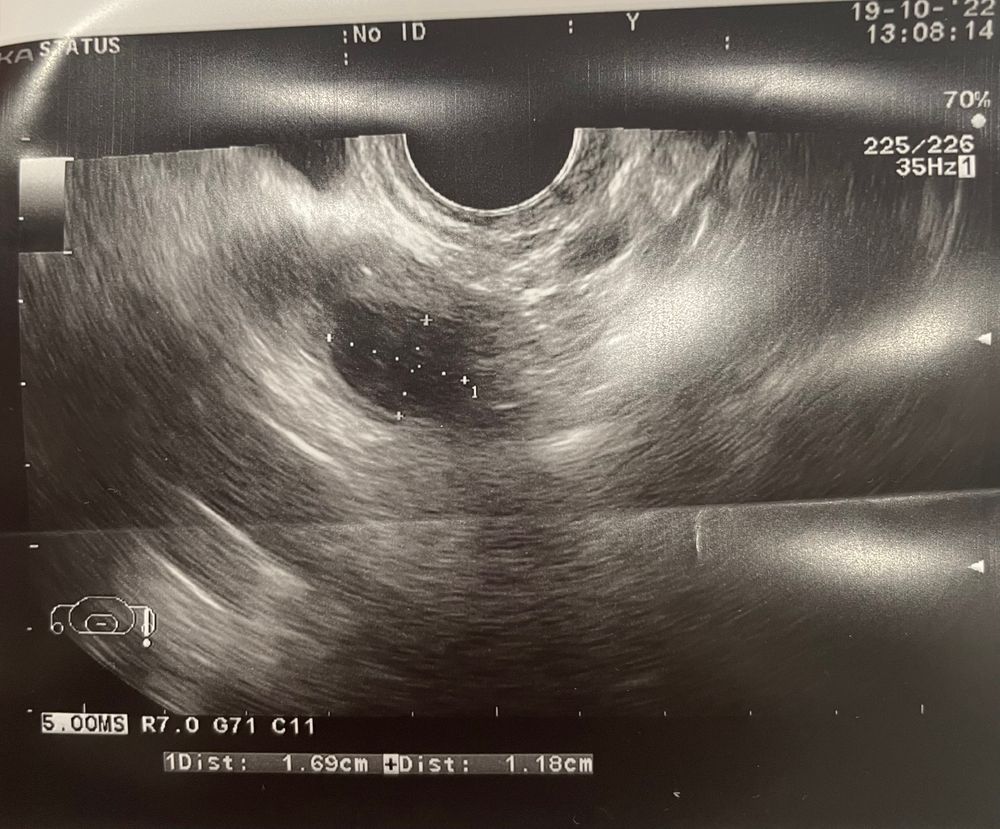

Этот месяц(ниже) узистка говорит, это фоликул скоро лопнет. Но мне непонятно, что у него внутри там что-то. Посмотрела по бб- как будто бы это киста? Она на том же месте что и в прошлом месяце. Вам тоже кажется что что-то не то?

из странного, ощущений овуляции не было особо

Alinnas, киста образовывается Из-за того что дф не смог лопнуть (гормона не хватило), и этот фолликул образовался в кисту. На первом узи фолликул, на втором уже из этого фолликула киста. Но , что меня смущает, фоликул должен достичь размера 20-23 мм что бы лопнуть, а тут какие-то маленькие размеры. А зачем знать что внутри?

У фолликулов контуры ровные, это больше на жт похоже

Очень похоже на кисту